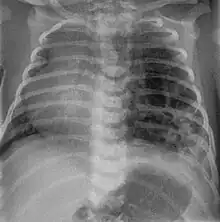

Foreign body aspiration

Foreign body aspiration is a major cause death in young children due their underdeveloped swallowing coordination. Young children most commonly ingest toys, coins, or food.[21] On chest x-ray, the most frequent sign is air trapping that can lead to a mediastinal shift. Atelectasis and pneumothorax may also occur in the setting of foreign body aspiration. The diagnosis is made in conjunction with clinical symptoms and confirmed and treated with bronchoscopy. [22]